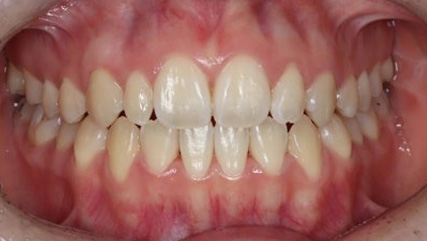

上顎前突といわれ、上顎の前歯が唇側に出ている状態を言います。

前歯が出ることで見た目の問題もありますが、口を閉じることができない、口呼吸をしてしまう、外傷などのリスクがあります。

日本人に叢生の次に多い不正咬合と言われており、自然に治ることはありません。また上の前歯が出ている事だけが気になるかもしれませんが、多くの場合、上顎の奥歯の位置に問題があることが多く、部分矯正でなく根本的な治療をした方がいい場合が殆どです。

口を閉じることができないことで、鼻呼吸でなく口呼吸をしてしまい、結果、成長期の場合顎の骨の成長を邪魔してしまうとも言われております。その他、口呼吸はアトピーなどを含むアレルギー症状の悪化、風邪を含むウイルス性の感染症にかかりやすいなどのリスクも増大してしまいます。

歯並びだけでなく全身への影響も多い為、早期の治療をおすすめ致します。